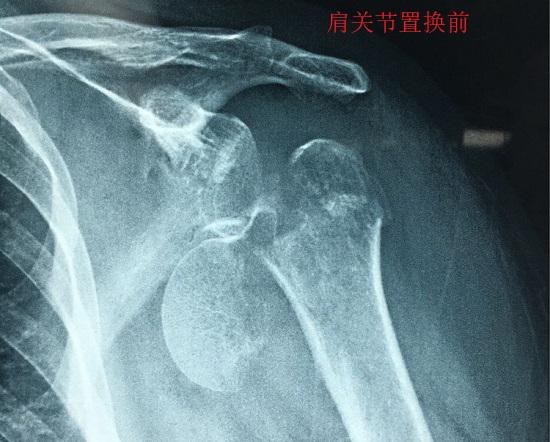

根据置换范围的不同,可将肩关节置换术分为全肩关节置换术(包括反球全肩关节置换术)、半肩关节置换术、肱骨头置换术等类型。笼统来讲,这几种置换手术的主要方法如下。

全肩关节置换术是指采用人工假体替换肱骨头和关节盂的手术,需要在肱骨和肩胛骨两端分别植入假体,有常规术和反球置换(球窝在肱骨一侧、球头在肩胛一侧,与正常的盂肱关节构造刚好相反)两种类型。半肩关节置换则只需要根据情况对肱骨头或盂窝构造进行置换,手术范围更小、难度更低。肱骨头置换术则只是对肱骨头进行置换。